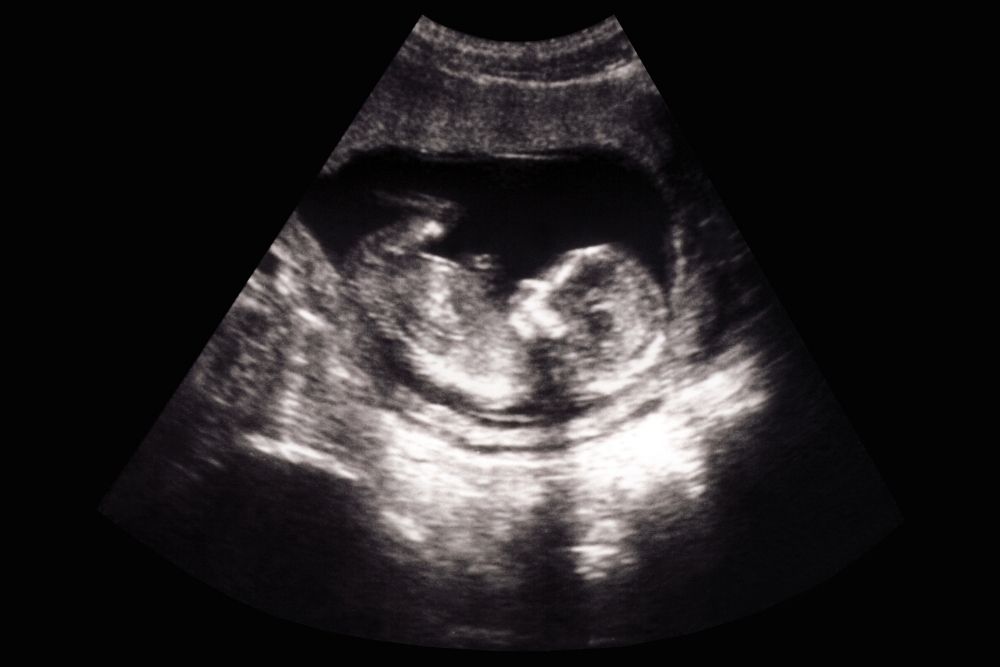

Obstetrical

Dating US, Nuchal Translucency, Detail Anatomy, Growth & Fluid